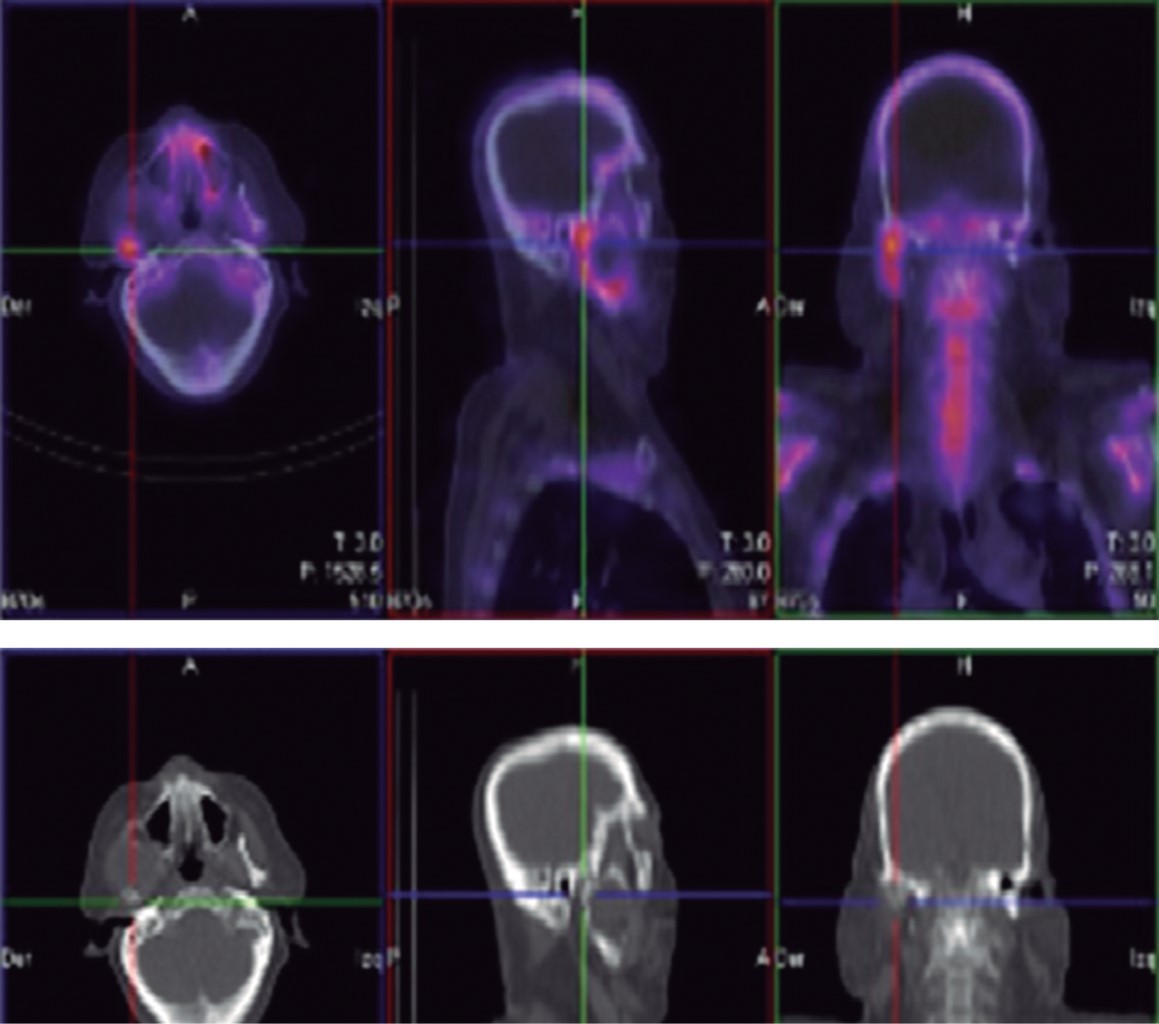

Inició padecimiento 19 meses previo a su primera valoración refiriendo chasquido súbito tras apertura máxima de la cavidad bucal, presentando dolor y aumento de volumen en la región posterior de la mandíbula derecha. En ortopantomografía se observa una zona radiolúcida, multilocular que abarca la rama ascendente derecha de la mandíbula y porción posterior del cuerpo mandibular con desplazamiento de tercer molar hacia borde cervical mandibular (Figura 1). En tomografía computarizada se observa lesión patológica multilocular que abarca la rama ascendente de la mandíbula, apófisis coronoides y hasta el cuello del cóndilo, la de mayor diámetro es de 35 × 32 mm con perforación de corticales casi en su totalidad y expansión de las corticales residuales (Figura 2). Se procede a realizar toma de biopsia incisional con un resultado de ameloblastoma folicular con datos de atipia celular (Figura 3), por lo que se decide solicitar gammagrama óseo que muestra una captación anormal en la rama mandibular derecha desde el cóndilo que correlacionan con la tumoración presente, así como un resultado negativo a la extensión metastásica ósea (Figura 4). Se decide realizar hemimandibulectomía y colocación de placa de reconstrucción con componente condilar. Se solicita estereolitografía para la preconformación de la placa de titanio y así disminuir el tiempo transoperatorio y márgenes de error en su colocación (Figura 5). Bajo anestesia general balanceada (AGB) se realizó fijación intermaxilar con ayuda de tornillos y cadena elástica. Se hizo incisión submandibular, se diseco el tejido por planos hasta llegar al hueso mandibular, se procedió a realizar hemimandibulectomía derecha, posteriormente se colocó placa de reconstrucción (Medartis MODUS®) con bloqueo y dispositivo condilar para reconstruir el cuerpo y rama mandibular (Figura 6), se verificó la oclusión, y el ajuste de la placa mediante toma de radiografía de control transoperatoria (Figura 7), se suturó por planos con sutura Vycril 3.0 y Polipropileno 5-0 para confrontar tejidos. El postoperatorio cursa sin complicaciones, por lo que se decide su egreso hospitalario para continuar su tratamiento por consulta externa en servicio de cirugía maxilofacial (Figura 8). El resultado histopatológico de la muestra completa reporta un espécimen formado por islas y cordones de epitelio ameloblástico de aspecto folicular y acantomatoso y displasia leve en un tejido conectivo fibroso denso bien vascularizado. Dos años después del procedimiento quirúrgico el paciente se encuentra asintomático y sin datos clínicos o radiográficos de recidiva.

Figura 4